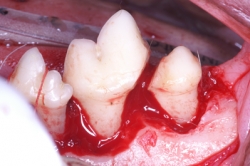

La periodontitis se clasifica como “Periodontitis leve” cuando el tejido óseo se ha destruido máximo en el tercio cervical; “Periodontitis moderada” cuando la destrucción ósea ha llegado al tercio medio de la raíz y “Periodontitis severa” cuando la destrucción ósea ha llegado al tercio apical de la raíz. La movilidad dental ligera aparece en la periodontitis moderada y la movilidad dental excesiva aparece en la periodontitis severa.